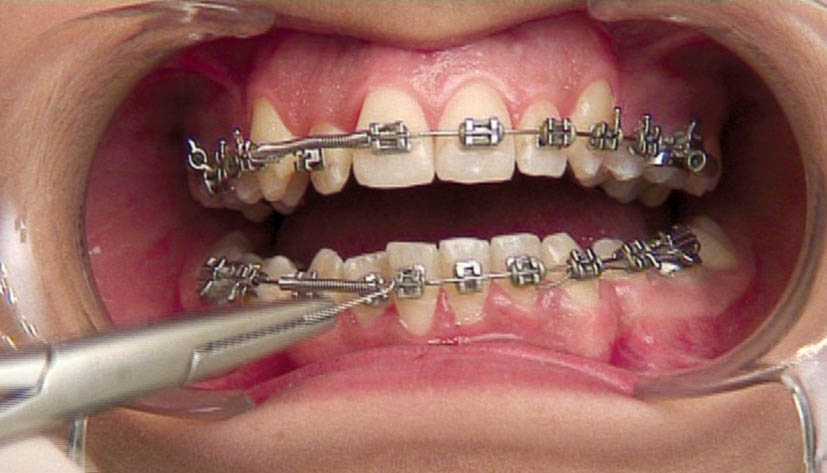

ضمناً دو قطعه یک میلیمتری هم جدا کنید و در پشت براکت کانین بگذارید (شکل 187-1) تا بعد از دو ماه که نیروی فنر اصلی کاهش یافت بتوانید با اینها، فنر اصلی را فعال کنید (شکل 188-1) تا مجبور به صرف وقت زیاد برای تعویض کل مجموعه نشوید.

روی براكت سانترال و کانین را با سیم لیگاچور میبندیم تا چرخش ایجاد نشود (شکل 189-1) چون سیم لیگاچور، آرچ وایر را روی براكت محكمتر از اورینگ نگه میدارد.

شکل 187-1: پشت کانین دو قطعه از فنر کلوز به طول 1mm برای فعال کردن در ماههای بعدی قرار دهید.

شکل 188-1: اضافه کردن قطعه فنر کمکی برای فعال کردن فنر در ناحیه لترال

شکل 189-1: وایر لیگاچور کردن دندانهای پایه فنر برای جلوگیری از چرخش آنها